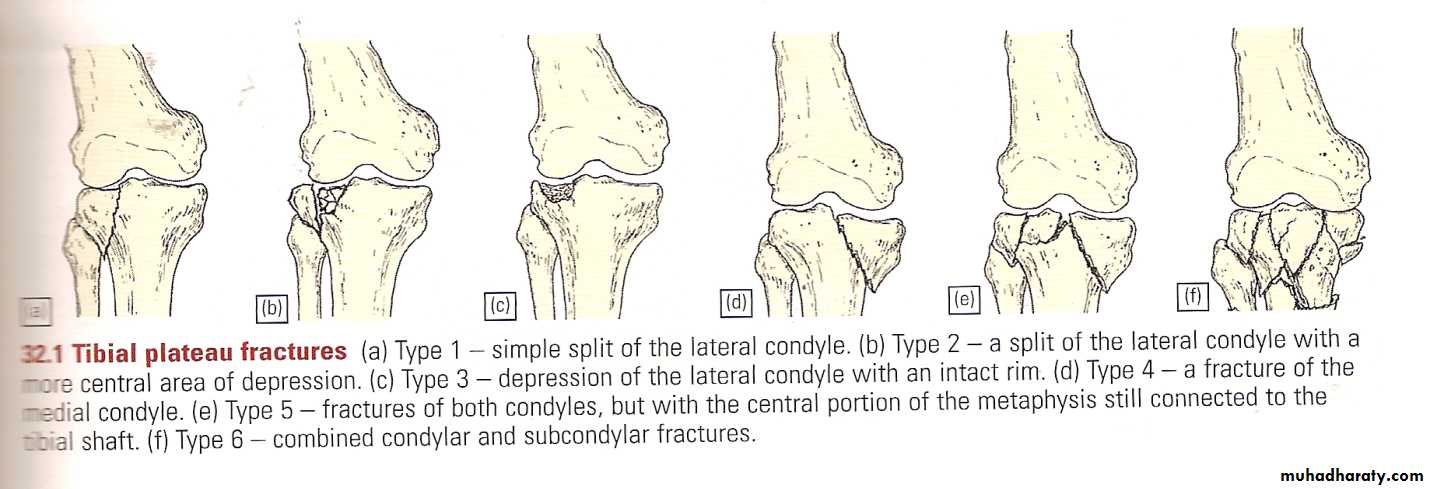

Tibial plateau fractures

Mechanism: medial or lateral bending force with axial loads, e.g. bumper fracture.

X-ray:

One or both condyles may fracture with varying degrees of comminution.

C-T:

scan in complex fractures.